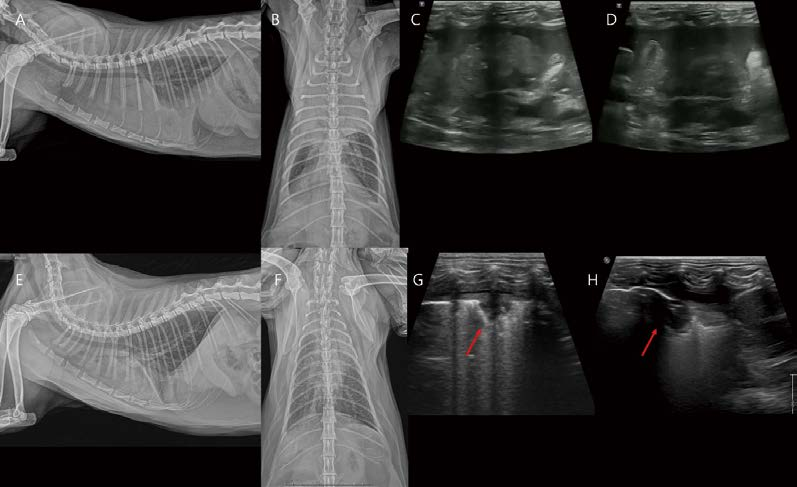

14살 중성화 암컷 4.93kg DSH cat이 식욕부진, 기침 증상으로 내원하였습니다. 흉부방사선 검사 외측상에서 심장의 cranioventral part, 복배상에서 우측 전엽에서 focal하게 기관지, 간질, 폐포의 혼합 침윤 소견이 관찰됩니다(A, B). 흉부 초음파에서 focal consolidation 영역이 관찰되는데, 확장된 기관지로 생각되는 tubular 구조물 내부로 hypoechoic fluid or materials이 채워져 관찰됩니다. 유의적인 혈관 이상 소견은 관찰되지 않습니다(F). CT 검사에서 우측 전엽의 일부에서 bronchial wall thickening, focal한 bronchiectasis, tubular dilated bronchi 내부로 homogeneous hypoattenuating mucoid impaction(mucus plugging) 소견이 관찰됩니다. 사람 asthma 환자에서 잘 관찰되는 finger in glove sign과 유사하게 관찰됩니다(C, D, E, G, H, I). 이 저감쇠 영역은 조영 증강 없이 30~60 HU number로 관찰됩니다. 지방 밀도는 아니어서 exogenous/ endogenous lipoid pneumonia 가능성은 낮게 생각됩니다. Pulmonary hyperinflation, air- trapping, bronchial luminal narrowing 등은 관찰되지 않습니다.

[대한수의사회지 24.png

Feline chronic asthmatic bronchitis 가능성, 종양 가능성, 또는 다른 감염성 질환 배제를 위해 bronchoalveolar lavage를 실시하였습니다. 세포학적 검사에서 호중구, 호산구 모두 주로 관찰되며, 종양성 변화는 관찰되지 않았습니다. PCR, 배양 검사 모두 음성으로 확인되었습니다. 흔히 하부 호흡기 질환을 크게 2개의 카테고리로 분류하는데, 고양이 asthma는 spontaneous reversible bronchoconstriction, airway remodeling, eosinophilic airway inflammation을 보이고, 고양이 chronic bronchitis는 airway thickening, excessive mucus production, neutrophilic inflammation을 보입니다. 그러나 이 환자처럼 세포학적으로도 eosinophilic, neutrophilic inflammation 둘 다 관찰되고, 영상학적으로도 소견이 overlapping되는 chronic asthmatic bronchitis 증례가 많습니다. 따라서 feline chronic asthmatic bronchitis에 준해서 스테로이드 포함 대증 치료를 진행하였습니다. 환자는 내과적 치료에 잘 반응하여 기침, 식욕, 활력 모두 개선되었으며, 흉부 방사선 검사에서 병변의 범위와 밀도가 약간 감소(병변이 아직 남아 있음) 하였습니다. 그러나 6개월 후, 기침이 다시 증가하고, 호흡하는데 불편함을 호소하였습니다. 흉부 방사선에서 우측 전엽 침윤의 범위와 밀도 모두 유의적으로 증가하여 종괴 양상으로 관찰됩니다(A, E. 사진 C는 6개월 전 초진 시, 사진 D는 스테로이드 처치 후, 사진 A, E는 초진 6개월 후). 병변은 폐초음파 검사에서 예전보다 크기가 크고 균질한 저감쇠 종괴 양상으로, bronchial wall, 혈관 구조 모두 소실되어 관찰됩니다(G). CT를 재촬영했을 때 석회화된 기관지벽의 right lateral, ventral로 다소 저감쇠의 종괴가 bulging되어 관찰됩니다(B, F, H, I). 초음파 가이드 FNA에서 pulmonary lymphoma가 고려되었고, 종괴를 포함한 우측 전엽절제술을 실시하였습니다. 조직병리학 검사에서 폐종괴는 괴사, histiocytic inflammation, multifocal bronchiectasis with mucus impaction and osseous metaplasia를 동반한 poorly differentiated round to polyhedral cell neoplasm로 나왔습니다. 추가 면역 염색(CD3, Pax-5, Iba-1, E-cadherin)이 추천되어 진행하였고 diffuse large B cell lymphoma로 확진하였습니다.